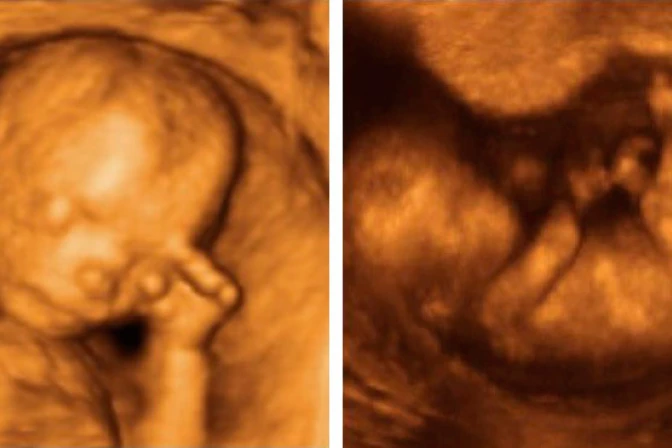

Para realizar la investigación, los científicos británicos utilizaron ecografías en 4D, con las que observaron a 15 bebés y grabaron 342 ocasiones en las que se tocaron el rostro.

Las imágenes fueron captadas en cuatro etapas diferentes del embarazo, entre las semanas 24 y 36.